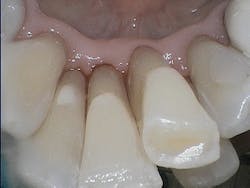

GBT denotes a method of biofilm management inclusive of the use of Air-Flow, Perio-Flow, and Piezon technologies (EMS). This systematic, predictable method of biofilm management features the intentional removal of biofilm as a definitive procedure, using low-abrasive powder in a novel air polishing device. Therapy is performed prior to the instrumentation of hard deposits.

As clinicians, we should prevent scratching surfaces or creating mineral loss while removing biofilm, both of which could ultimately leave the surfaces more plaque- or stain-retentive. Flemmig et al. reminded clinicians in a 2007 study that “abrasion on tooth surfaces might become substantial over time, when the cumulative effects of repeated instrumentation during SPT [supportive periodontal therapy] are considered.”1

Clinicians traditionally mechanically debride biofilm and calculus simultaneously using repetitive, overlapping strokes followed by polishing pastes. Thirty years ago, there weren’t many other options, but just like the technological advances in dentistry—e.g., digital radiographs, scanning devices to replace alginate impressions, and technology to move teeth with computer-generated trays—GBT is a system that replaces the antiquated methods of professional biofilm management. From a comfort perspective, GBT is ergonomic for the clinician and preferred by patients compared to biofilm management with ultrasonic or hand instrumentation.3

Another benefit of biofilm management via GBT is efficiency when implementing the eight-step system. Since clinicians remove biofilm from surfaces early on in the appointment, the need for overlapping, repetitive strokes using power or hand instrumentation is substantially reduced. Total debridement time is less, which allows extra time for additional services and patient education. The patient experiences less mechanical instrumentation with GBT, yet enjoys the optimal outcome of smooth, clean surfaces.